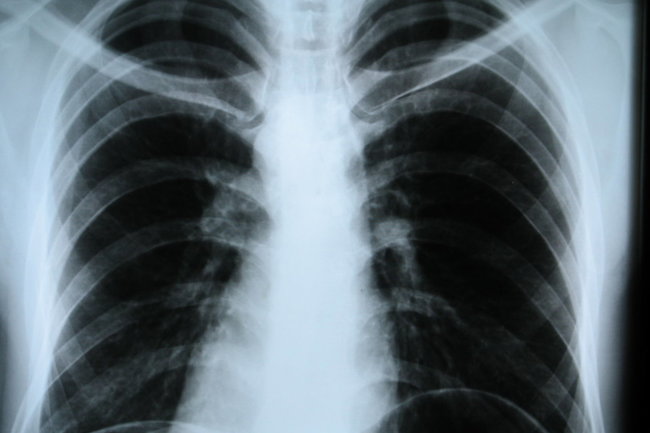

Уланкина уточнила, что процесс диагностики обычно стартует с лабораторных исследований и рентгенографии лёгких. Она порекомендовала обсуждать полученные результаты с терапевтом, который, при необходимости, может направить пациента к фтизиатру для более точного определения диагноза.